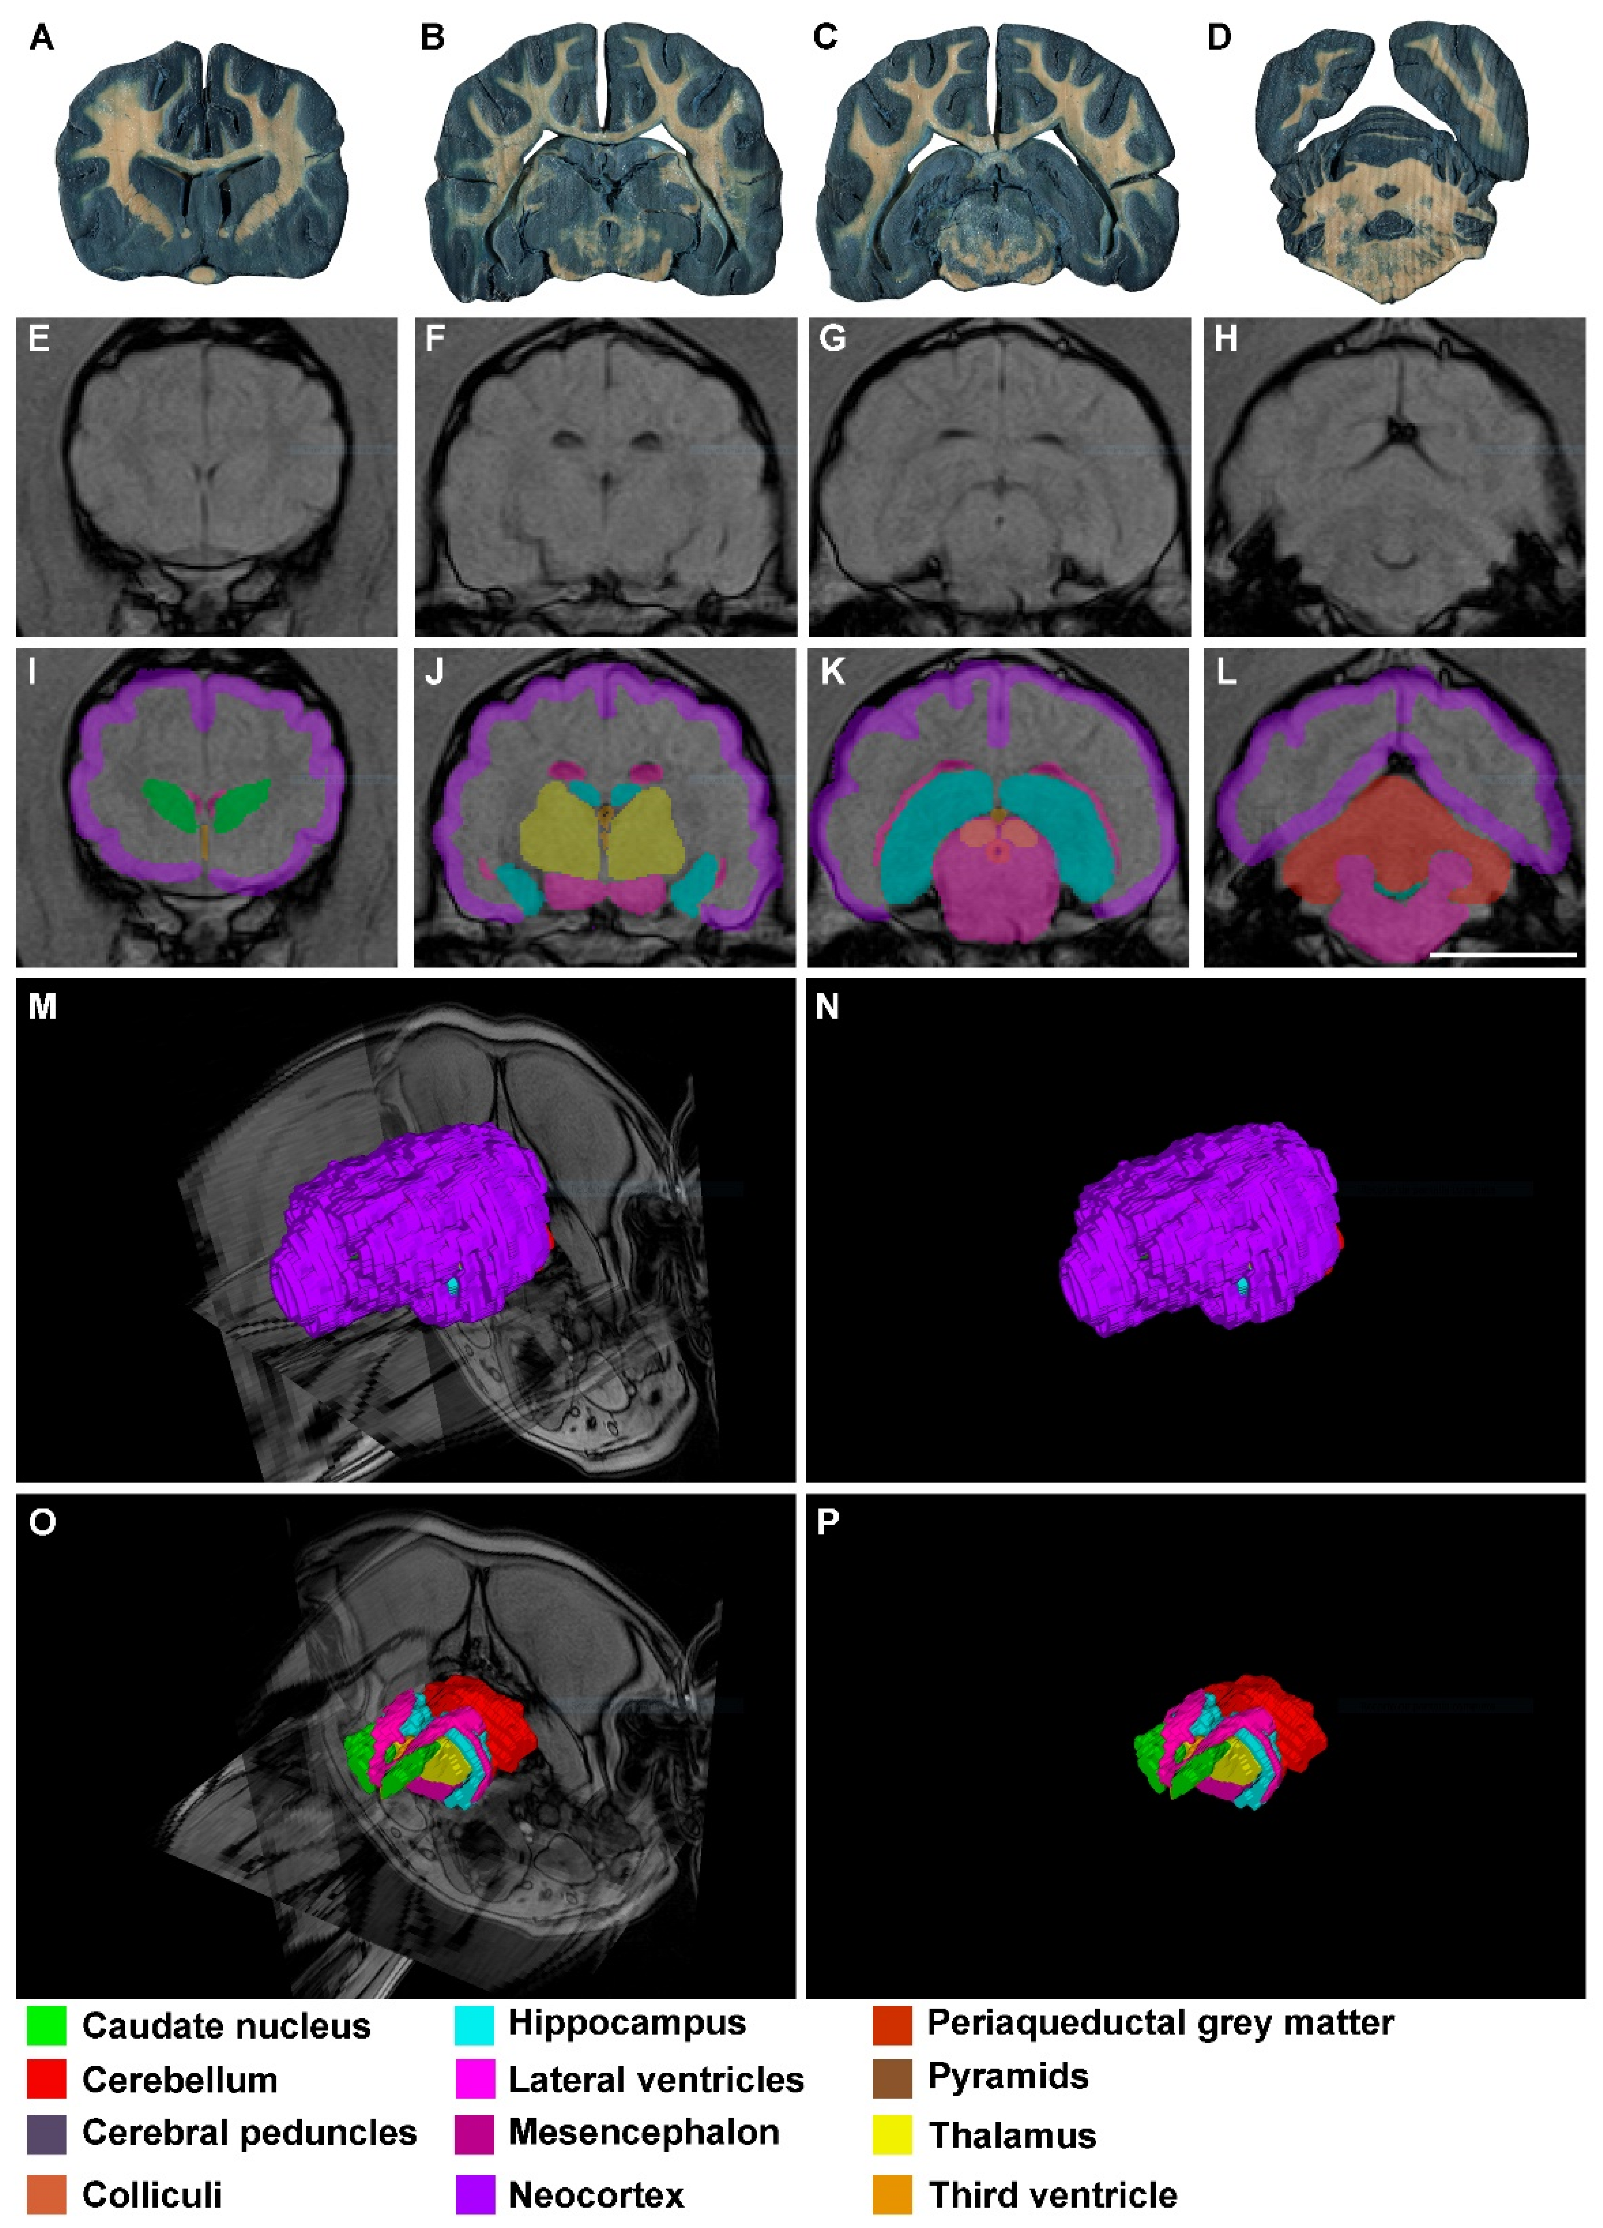

3. Results